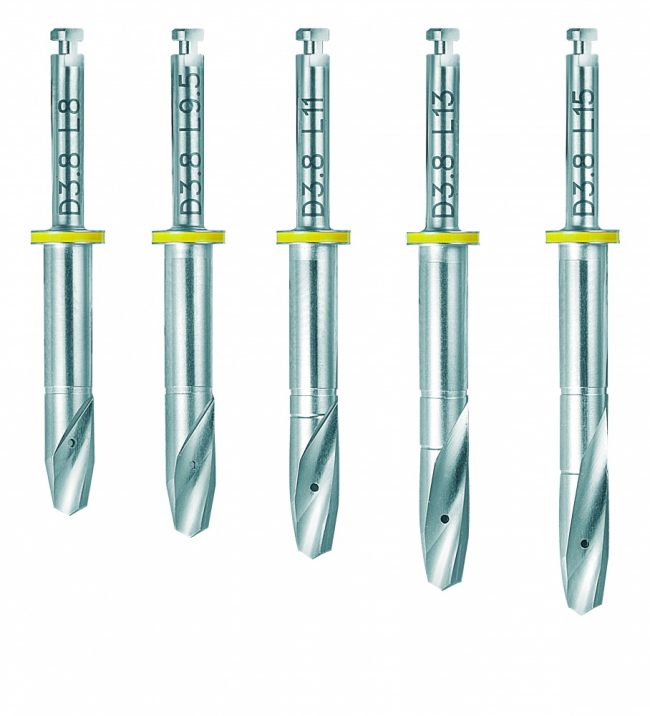

Отдельная тема — это тип фрез, используемых для подготовки лунки. Глобально, их можно разделить на два типа:

1. Фрезы с разметкой по глубине погружения. Таковыми являются фрезы в наборах Astratech:

или XiVE:

2. Фрезы, калиброванные по глубине погружения. Например, Nobel Biocare:

или всё тот же XiVE, но под навигационные системы:

Казалось бы, со вторым типом фрез работать проще — не нужно париться с глубиной погружения и следить за отметками. Однако, при работе в тесных условиях, с ними могут возникнуть сложности — рабочая часть фрезы, конечно, откалибрована по длине, а вот хвостовик (та часть, которая вставляется в наконечник) у всех фрез одинаковый. И, возможно, потребуется специальный удлинитель для того, чтобы подготовить лунку под имплантат правильно: